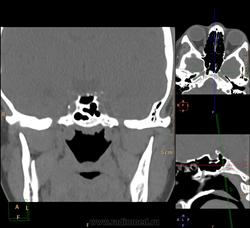

Вроде основных две, но разнообразные перегородки делят их на бОльшее количество:

Тут, например, 7 камер у одной пациентки: